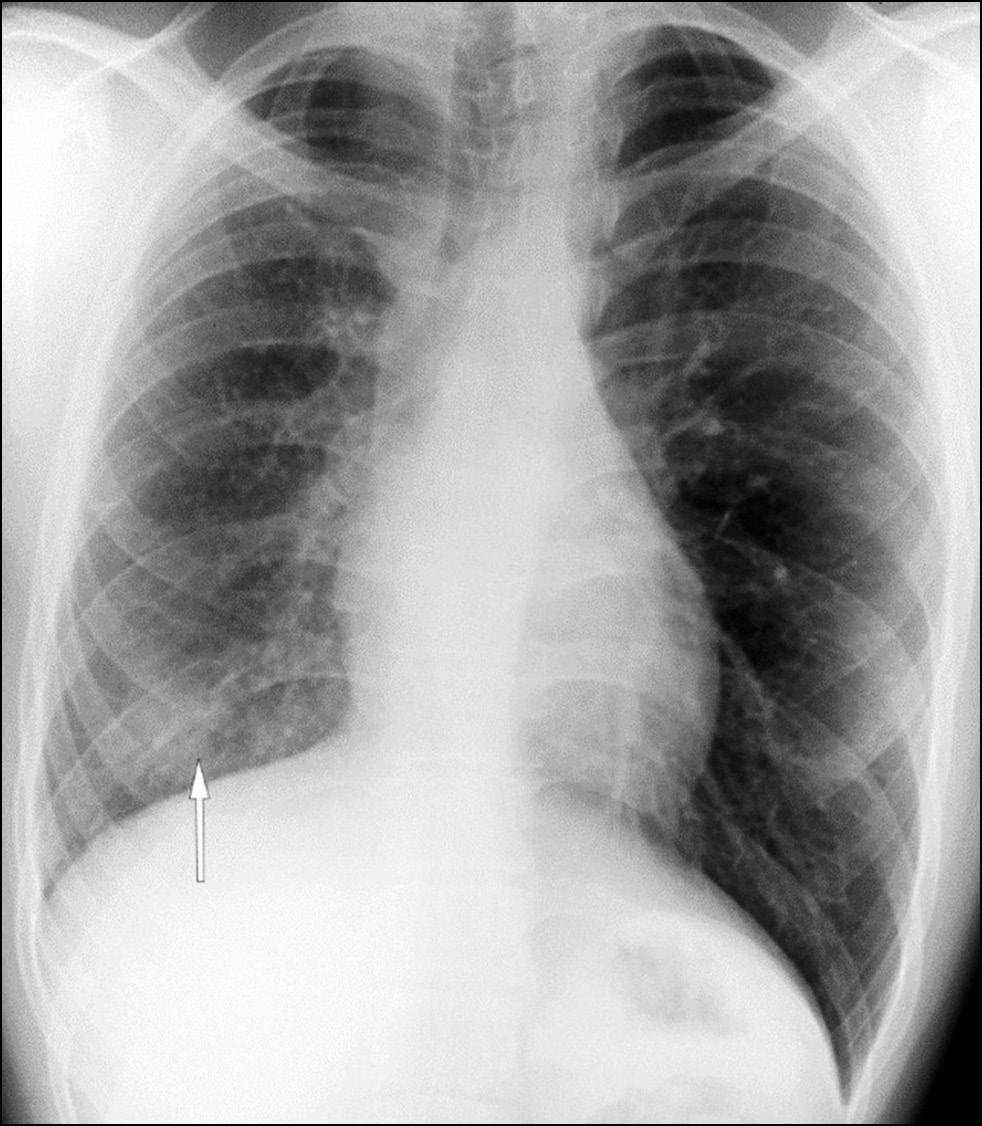

In 2020, a routine chest X-ray showed decreased right lung volume and a shaded, ill-defined lesion in the lower part of the right lung (Fig. 1). During examination, the patient presented no complaints.

Fig. 1. Lung X-ray. Decreased volume of the right lung; a shaded ill-defined lesion in the lower part of the right lung field (white arrow).